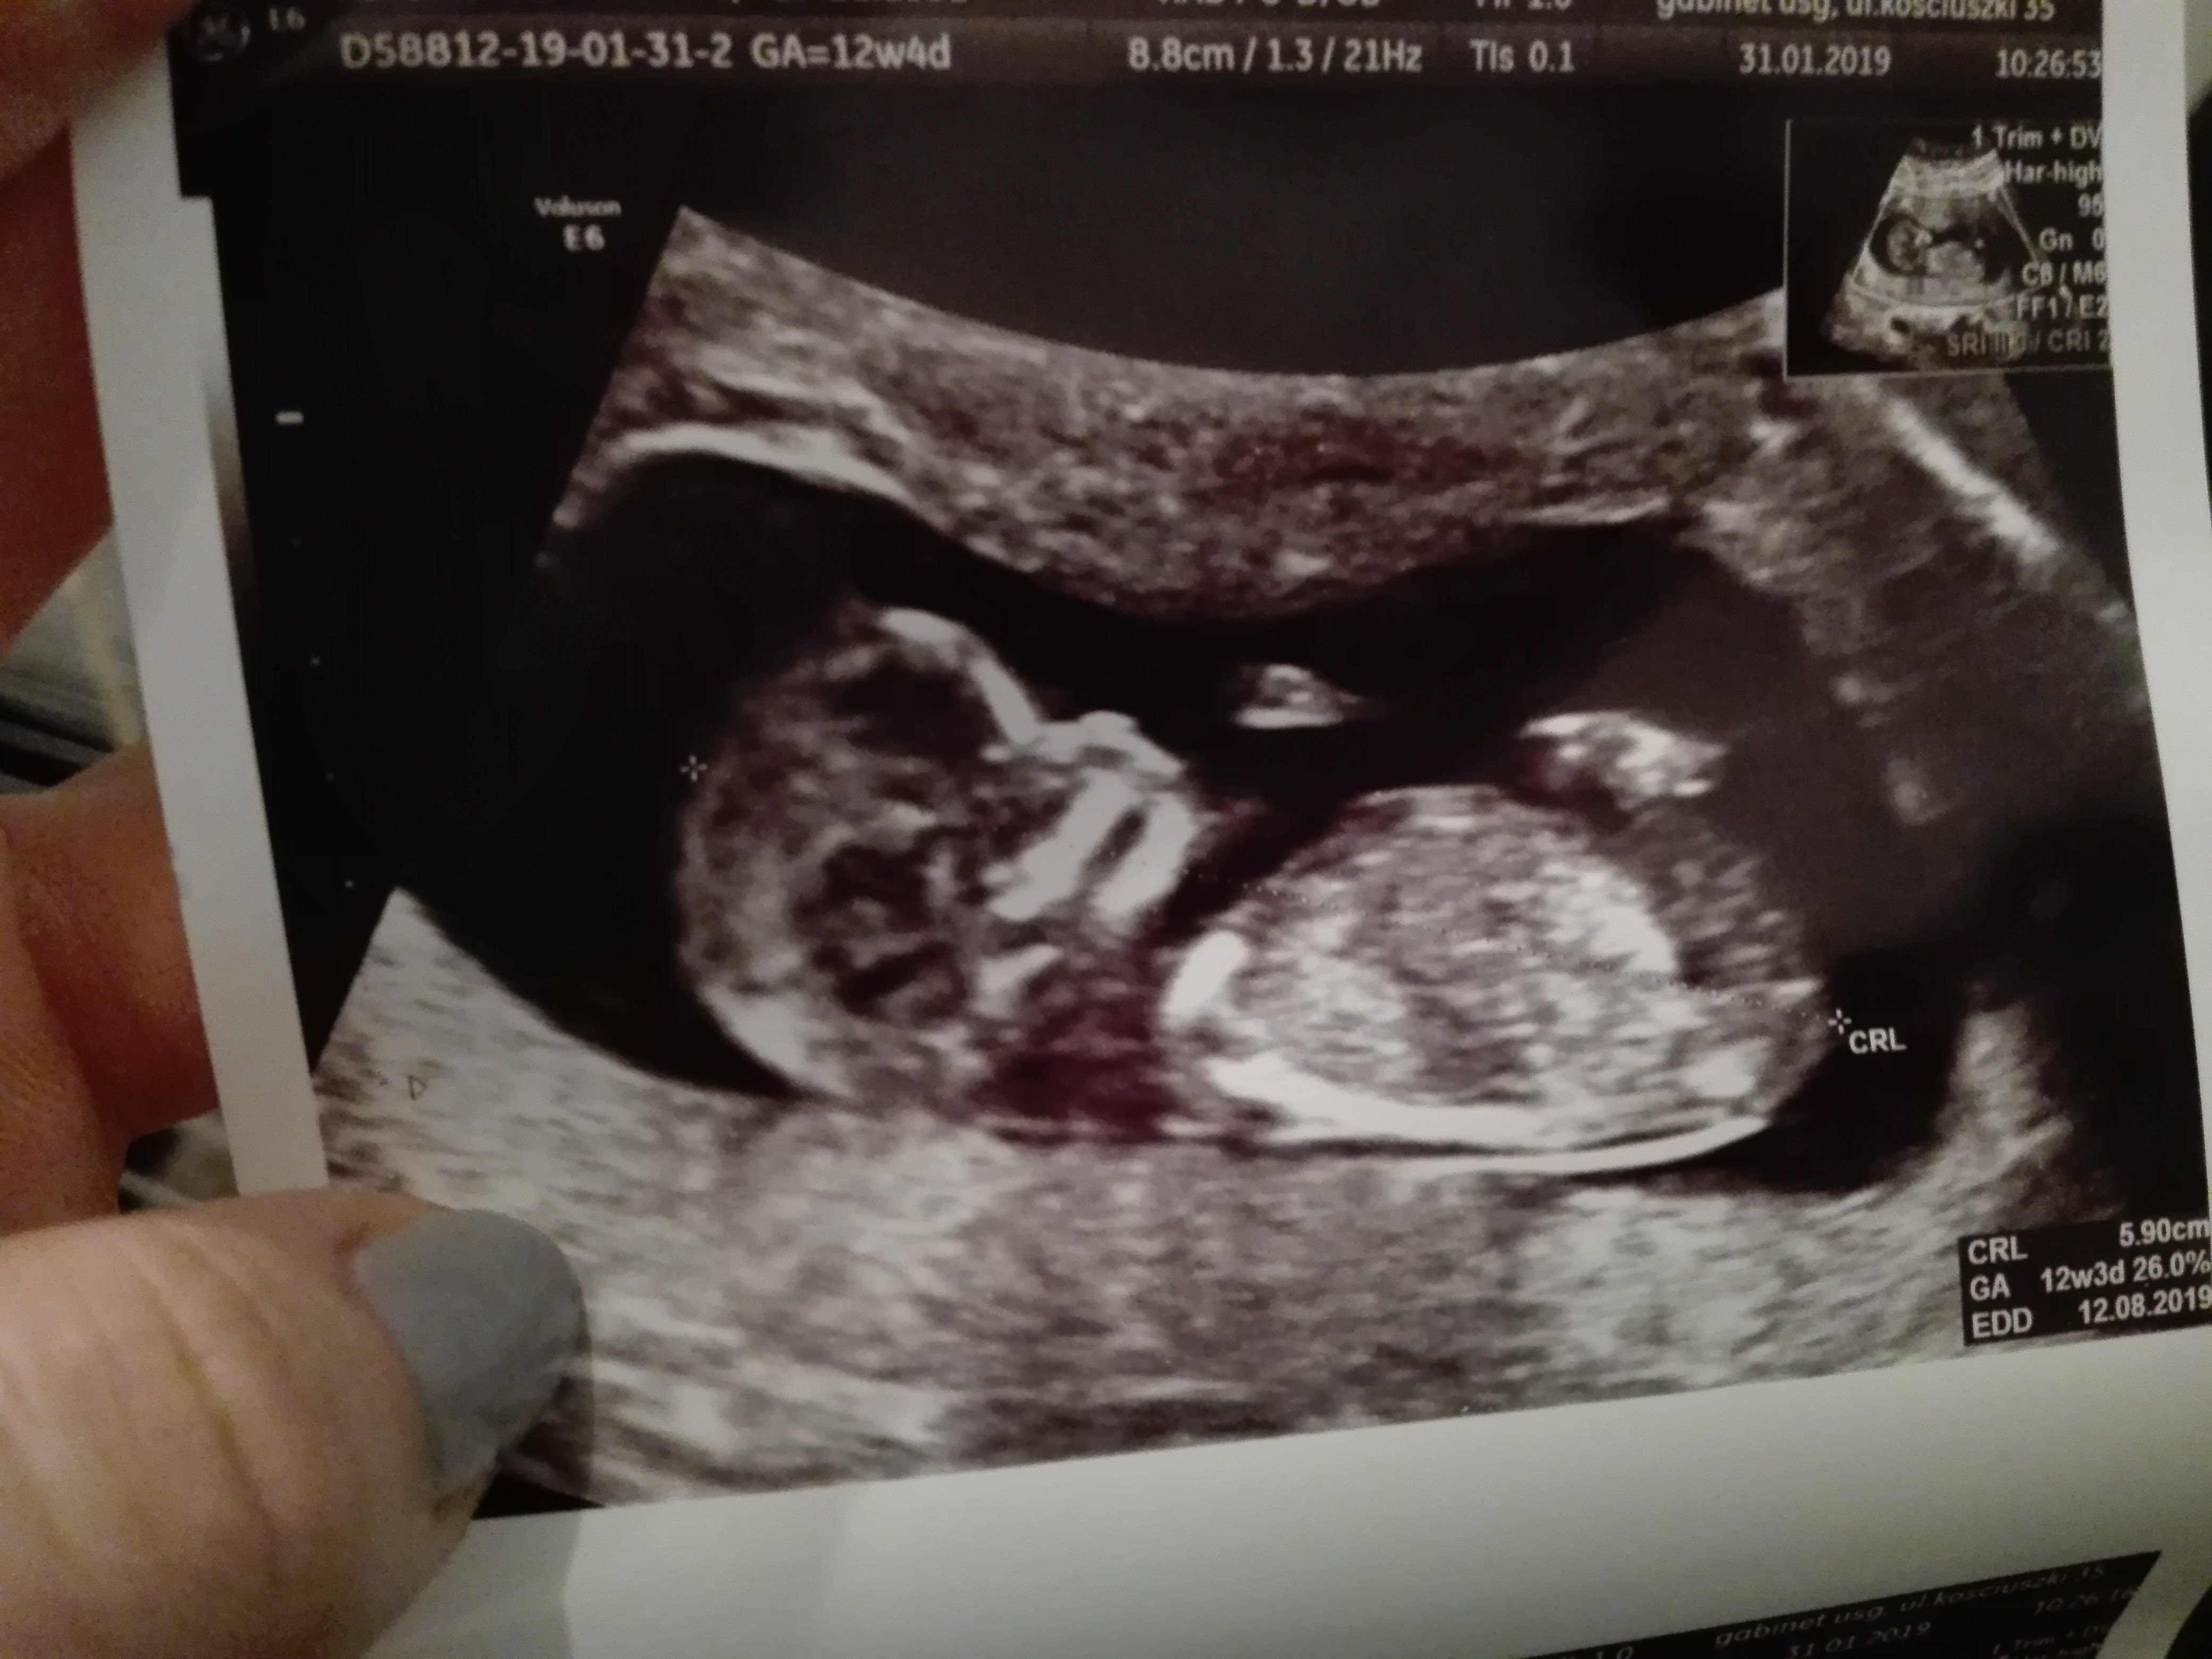

Czekam na jakąś konkretna wizyte, szukam genetyka i będę walczyc o dzidzie. Tyle na nia czekalam.....Zobacz załącznik 938849

3.3 przy normie ich usg do 2.5.Co znaczy powiększona ? Ile miałaś ? Może warto zasięgnąć porady innego lekarza ? Czasami zdarzają się takie jołopy co nie potrzebnie straszą a okazuje się, że z dzieckiem ok !